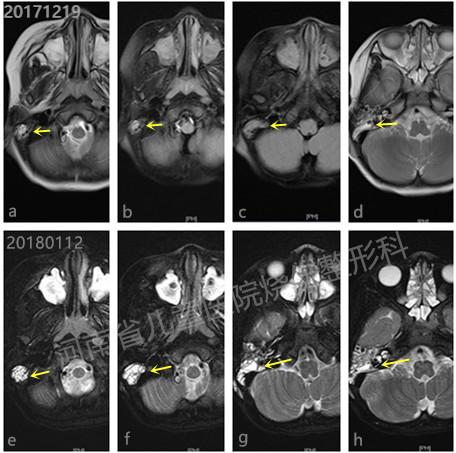

图2:a-d第一次磁共振检查因合并出血,病灶显示并不明显;e-f第二次磁共振检查提示明显病灶。